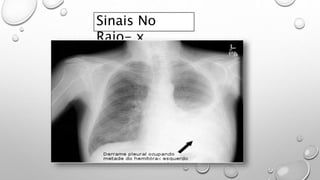

Sinais No

Raio- x

Setas indicando Sinal de Menisco.

Típico em derrame Pleural